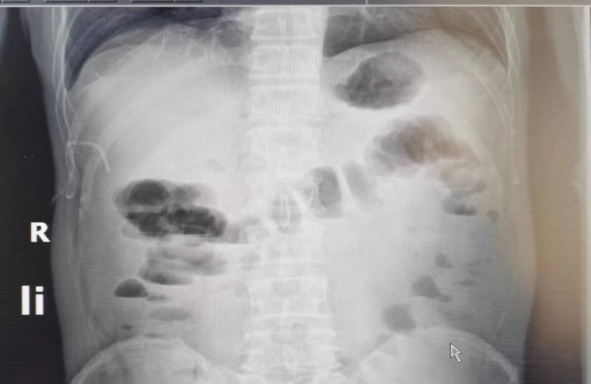

2022-06 腹部平片

右中上腹肠管扩张并少许气液平面,考虑肠梗阻。